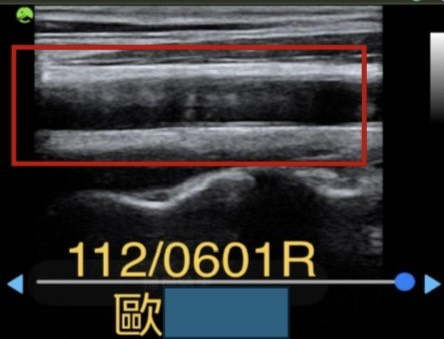

三個月後回診,檢查結果,原本的一坨大型斑塊已分解成散開的糊狀,血液送往腦袋流量明顯增加,如圖。頭暈重改善8成,睡眠變好,可入睡,一晚大概醒來1次,夢減少較模糊,睡醒精神不錯,夜尿1行。全身多處肌肉緊繃減輕8成,痠痛感減輕8成,安眠藥吃1/4。